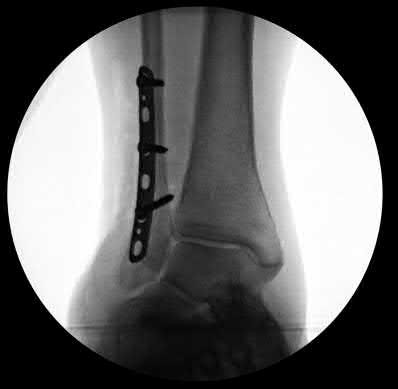

A 64-year-old woman is thrown off a horse, sustaining the injury shown in Figures A and B. She undergoes surgical fixation as seen in Figures C through E. What is the most commonly reported complication of this procedure?

The patient in the scenario has a 2-part proximal humerus fracture treated with a locking plate as seen in Figures A-E. The most common complication with the use of this implant is screw penetration. The terms screw cut out and penetration are often used interchangeably in the literature with cut out appearing more frequently in reports regarding intertrochanteric fractures.

Owsley et al retrospectively reviewed 53 proximal humerus fractures treated with locking plates and the same post-operative protocol. The most common complication was screw cut out or penetration, followed by varus displacement. They concluded that 3 and 4-part fractures in patients over 60 years have a higher incidence of failure.

Agudelo et al retrospectively reviewed 153 patients at a level-one trauma center treated with proximal humerus locking plates, investigating modes of failure for the implant. They determined that varus malreduction (head-shaft angle